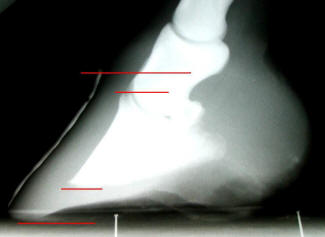

Fig. 1) 18tear old, domestic cadaver

with healthy hoof wall/P3 relationship (sound at death, died in accident).

It has adequate sole thickness and a very short hoof capsule. This healthy

combination is possible, because of the proper relationship between P3 and

the coronet.